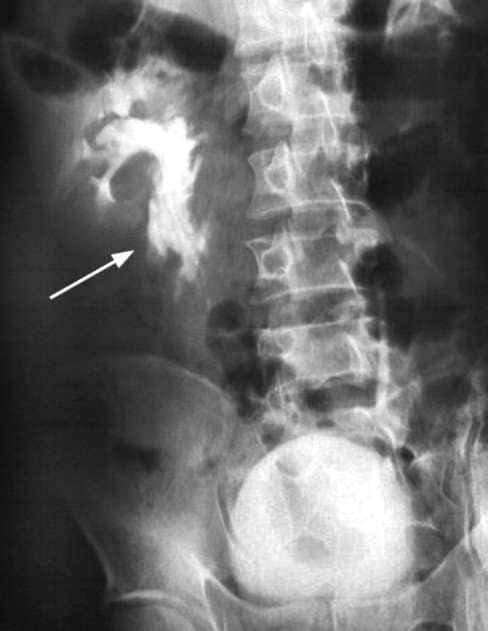

Таким образом, для того, чтобы выставить диагноз анурии, необходимо провести одно из фундаментальных исследований в урологии – выделительную (экскреторную) урографию. При этом, если моча не будет контрастироваться вообще, или ее можно будет увидеть только в полости почек, то это означает, что у пациента действительно имеет место анурия и ему необходимо провести дополнительный ряд исследований на выявления ее причины.

Анурия на экскреторной урограмме